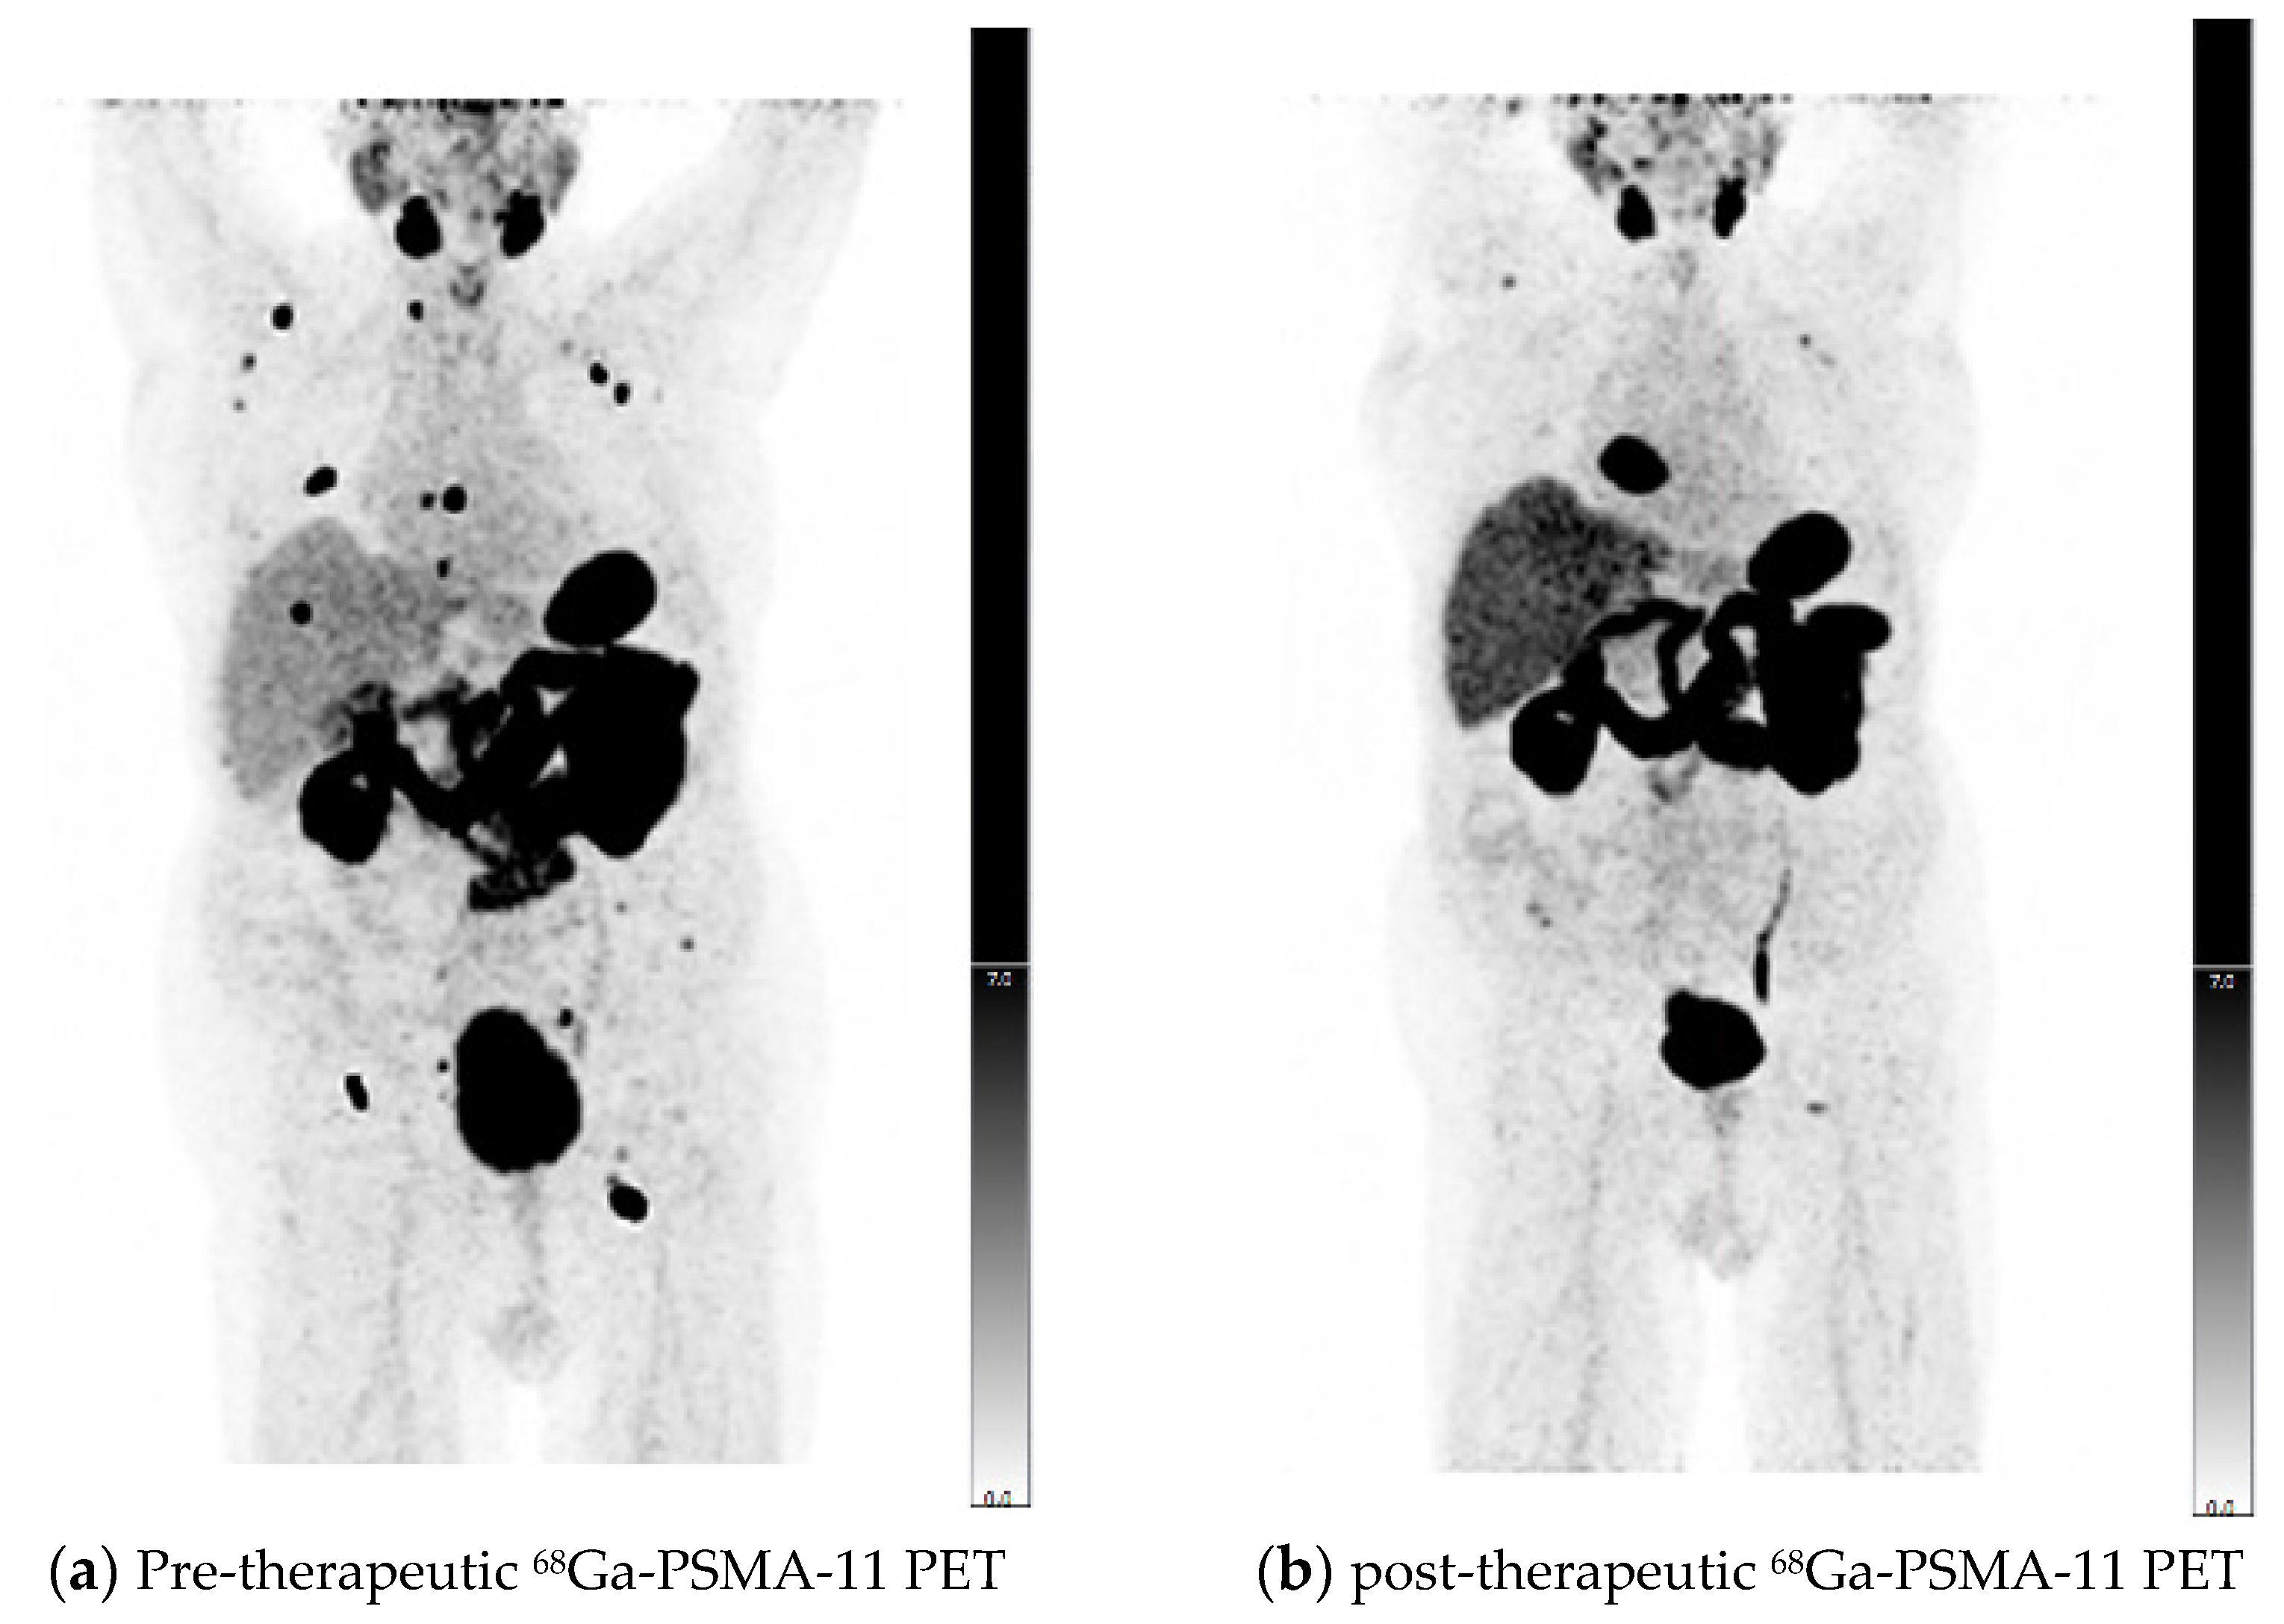

2.3. PET/CT Imaging